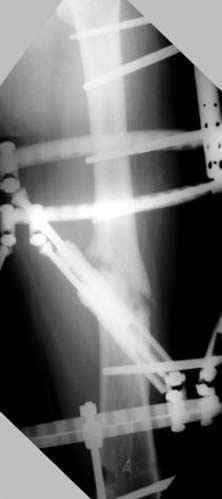

Интраоперционные N5 косая запирательная и N6 подвздошный снимок

пластическая модель; и коррекция бедра аппаратом Илизарова.

Имею другие снимки тоже, получится как отчет о моей работе.